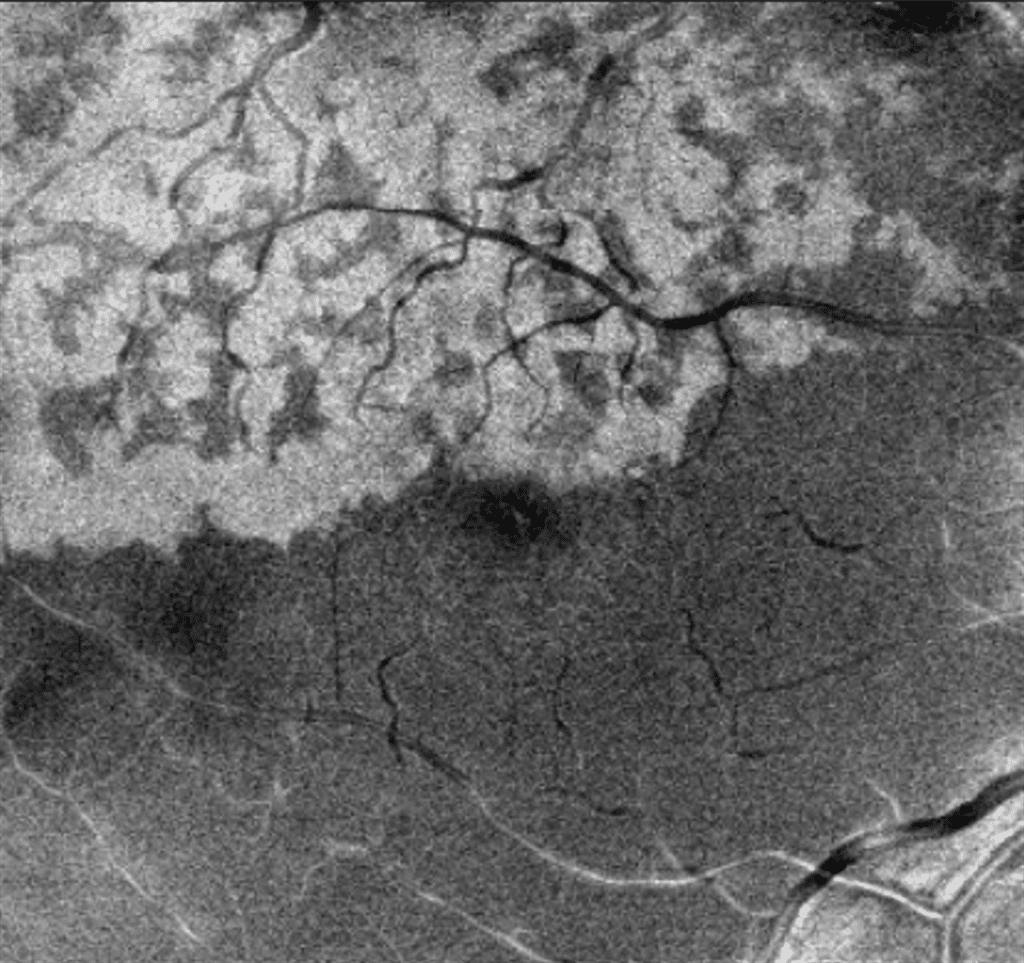

A healthy 43-year-old woman presented to the emergency department with sudden vision loss in her right eye. Ophthalmic examination revealed a visual acuity of 20/32 OD, 20/20 OS, and a normal anterior segment. Dilated fundus examination revealed diffuse venous dilation and tortuosity with associated intraretinal hemorrhage, indicative of a central retinal vein occlusion. Macular examination also revealed subtle retinal whitening localized to the superior aspect of the fovea. Cross-sectional spectral-domain OCT of the central macula revealed multifocal hyperreflectivity within the inner and middle retinal layers in a skip pattern with no macular edema, suggestive of paracentral acute middle maculopathy (PAMM) (see Figure 1). En face OCT angiography demonstrated the presence of a fern-like pattern of hyperreflectivity along the venules (see Figure 2). A follow-up examination one month later revealed attenuation of the PAMM lesions with inner nuclear layer thinning (see Figure 3,4).

In eyes with retinal vascular occlusion, PAMM can present in three morphological patterns – fern-like, globular, or arteriolar.1 The fern-like pattern is visualized with structural en face OCT and characteristically shows band-like hyperreflective lesions at the level of the inner nuclear layer in a perivenular distribution with periarteriolar sparing. Recent advances in the understanding of the inner and middle retinal microvasculature help explain why this pattern occurs. Venous flow through the deep capillary plexus, which is found at the outer limit of the inner nuclear layer, occurs radially through horizontal venules converging into a central vortex venule which then ascends to superficial retinal veins.2 Henceforth, in cases of increased resistance to venous outflow, greater hydrostatic pressure produces the greatest ischemia in the distal end of the deep capillary plexus, rendering the inner nuclear layer most vulnerable to ischemia. The hyperreflectivity seen on OCT is an indication of infarction caused by ischemia to the deep capillary plexus.